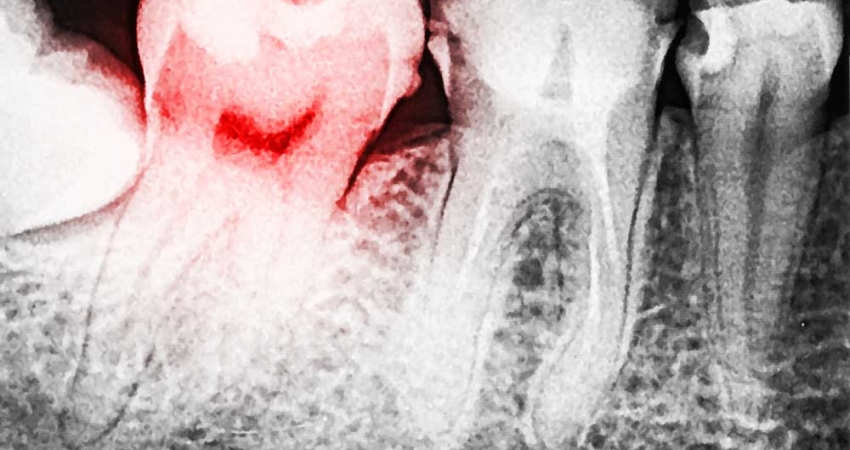

Çürük diş üzerindeki koyu renk ve oyuklarla kolayca tanınır. Fakat bazen çürük çukurcuğu gizli kalır ve diş hekimi ancak yardımcı tanı araçlarıyla (diş röntgeni gibi) teşhis koyabilir. Çürükler,bazen diş tüberküllerinin yani tümsekciklerin birbiriyle kesiştiği yerde veya dişin boyun kısmında görülür. Bazende iki diş arasında kalan gizli çürükler uzun süre fark edilmez. Diş çürüğünde diş hekimine başvurmayı gerektiren en önemli belirti ağrıdır. Ağrı, soğuk, sıcak, tatlı veya ekşiden olur. Ağrının şiddeti kişiden kişiye değişir ve etken ortadan kalkınca ağrıda geçer; fakat tedavi edilmeyen çürüklerde ağrılar bir süre sonra sürekli olmaya başlarlar. Ayrıca ağızda meydana gelen kokular çürüklerin habercisi olabilir.

Çürük, dişin yüzeyindeki mine tabakasından başlar ve ilerleyerek dentin tabakasına erişir. Dentin, mineden daha fazla organik madde içerir. Bu nedenle çürük bu tabakada daha çabuk yayılır. Çürüğün ilerleme hızı, kişiden kişiye ve dişten dişe çok değişir. Unutulmaması gereken mine ve dentin dişin bir savunma organı olduğudur.